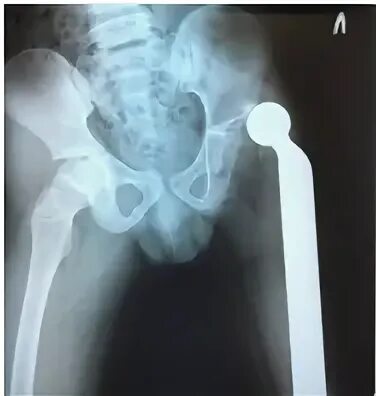

Эндопротез тазобедренного сустава мкб 10